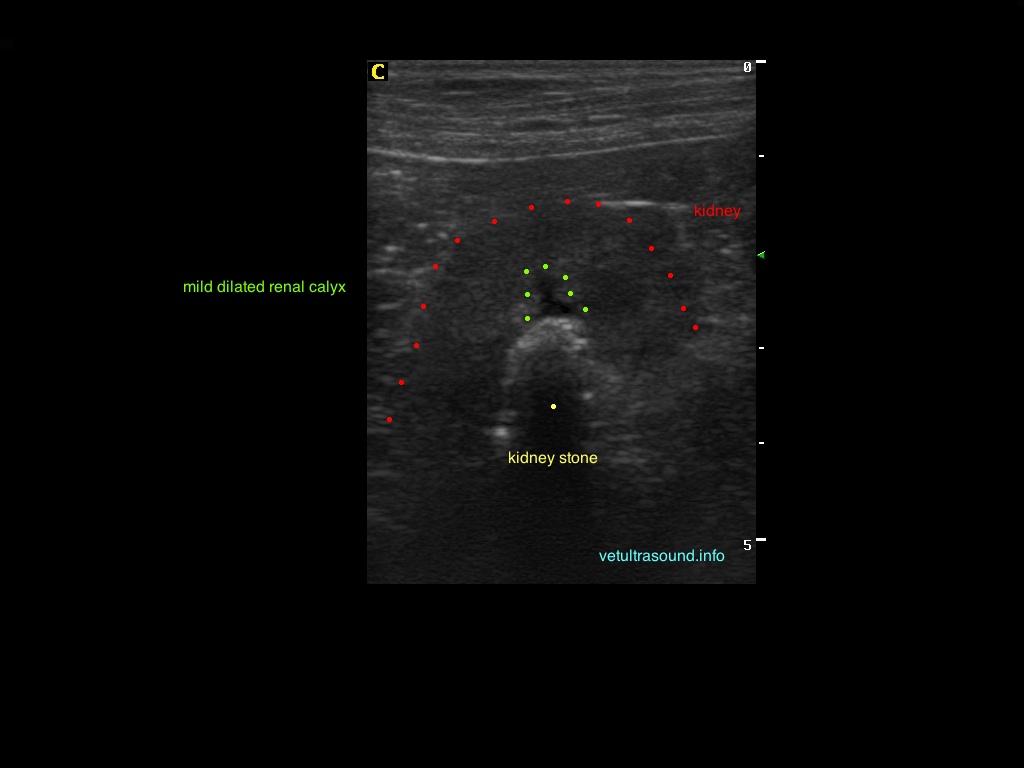

Ευρήματα: Παρουσία λίθου στην πύελο του αριστερού νεφρού ο οποίος καταλάμβανε όλη την κοιλότητά της και εκτεινόταν στο πρώτο τμήμα του ουρητήρα. Ο λίθος προκαλούσε ήπια διάταση του πυελοκαλυκικού συστήματος και του ουρητήρα. Αντίστοιχα στον δεξιό νεφρό βρέθηκε λίθος ο οποίος εντοπιζόταν μόνο στην κοιλότητα της νεφρικής πυέλου. Στην ουροδόχο κύστη βρέθηκε μικρή παρουσία ιζήματος.